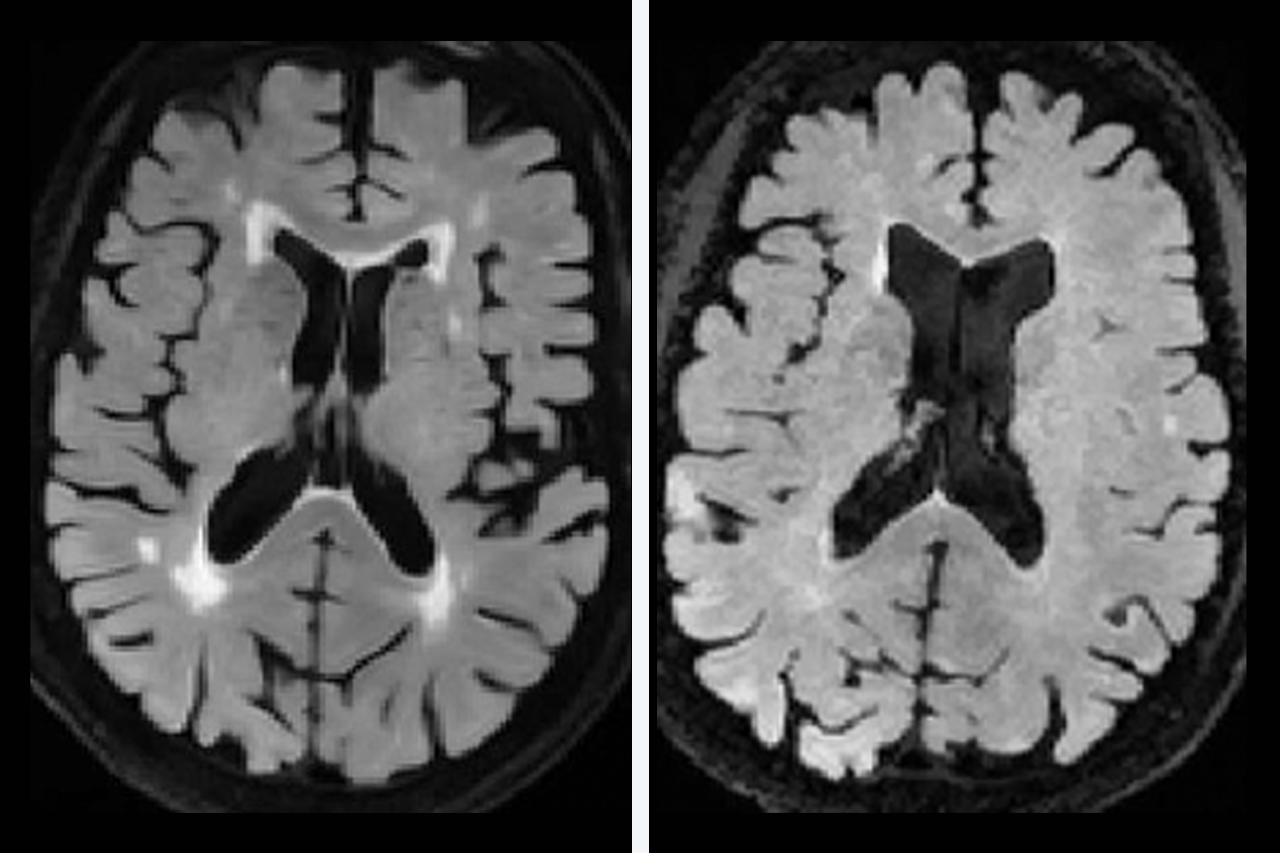

As we age, almost all of us develop changes in our brains’ white matter that show up on imaging as bright spots (white matter hyperintensities). These changes, or lesions, indicate damage to the white matter that is linked to cognitive and motor decline, dementia and stroke.

These images show how OHSU researchers are studying cerebrovascular disease, or conditions that affect blood flow to the brain.

MRI scans show that up to 97% of older people have some changes or lesions in their white matter, even if they don’t notice any mental or physical changes.

Researchers found that collagen thickness in the veins, not arteries, is a significant predictor of white matter lesions around the ventricles. Venous collagenosis likely reduces the body’s ability to clear fluid from between brain cells, resulting in abnormal fluid in the white matter that we see as lesions on MRI.